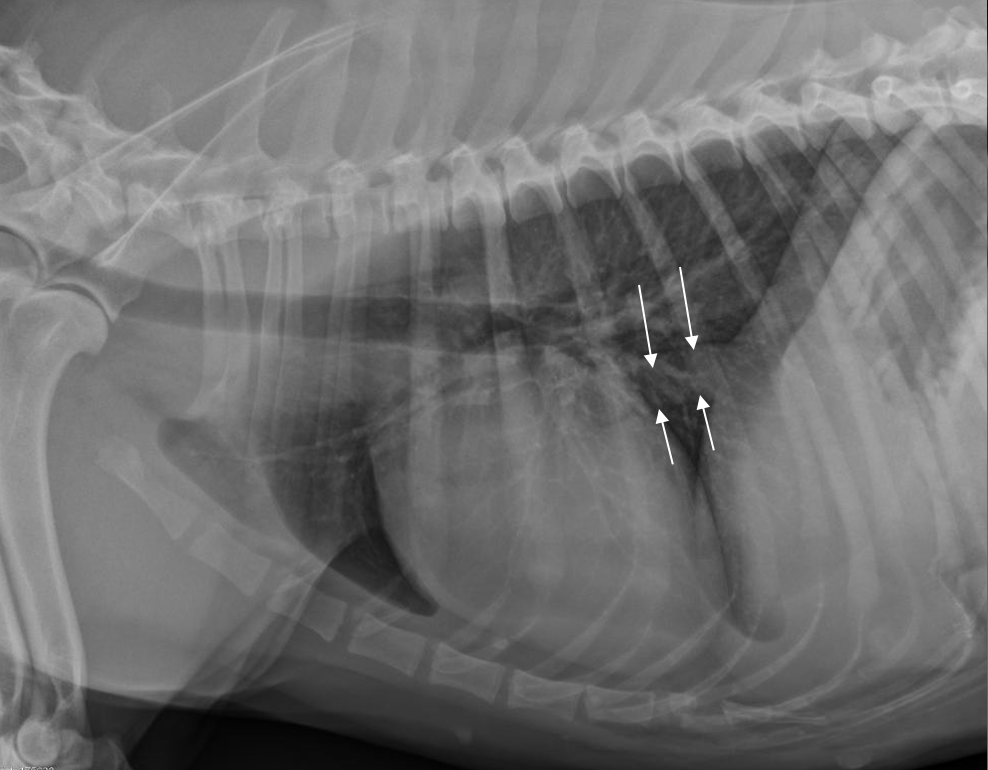

12

Q

Which structure is present at the location of the white arrows?

A

caudal vena cava